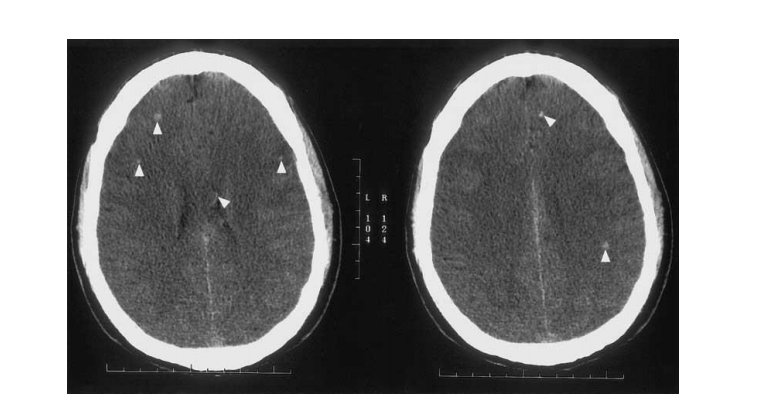

DAI được chia làm 3 mức độ: nhẹ, trung bình và nặng theo phân loại của Adams.

Nhẹ (grade 1): có sự thay đổi vi thể ở chất trắng của vỏ não, thể chai, thân não, và thỉnh thoảng ở

tiểu não.

Trung bình (grade 2): Các tổn thương khu trú, rõ ràng về đại thể ở thể chai.

Nặng (grade 3): Các tổn thương ở grade 2, kèm thêm tổn thương ở thân não (thường ở cuống tiểu

não trên).